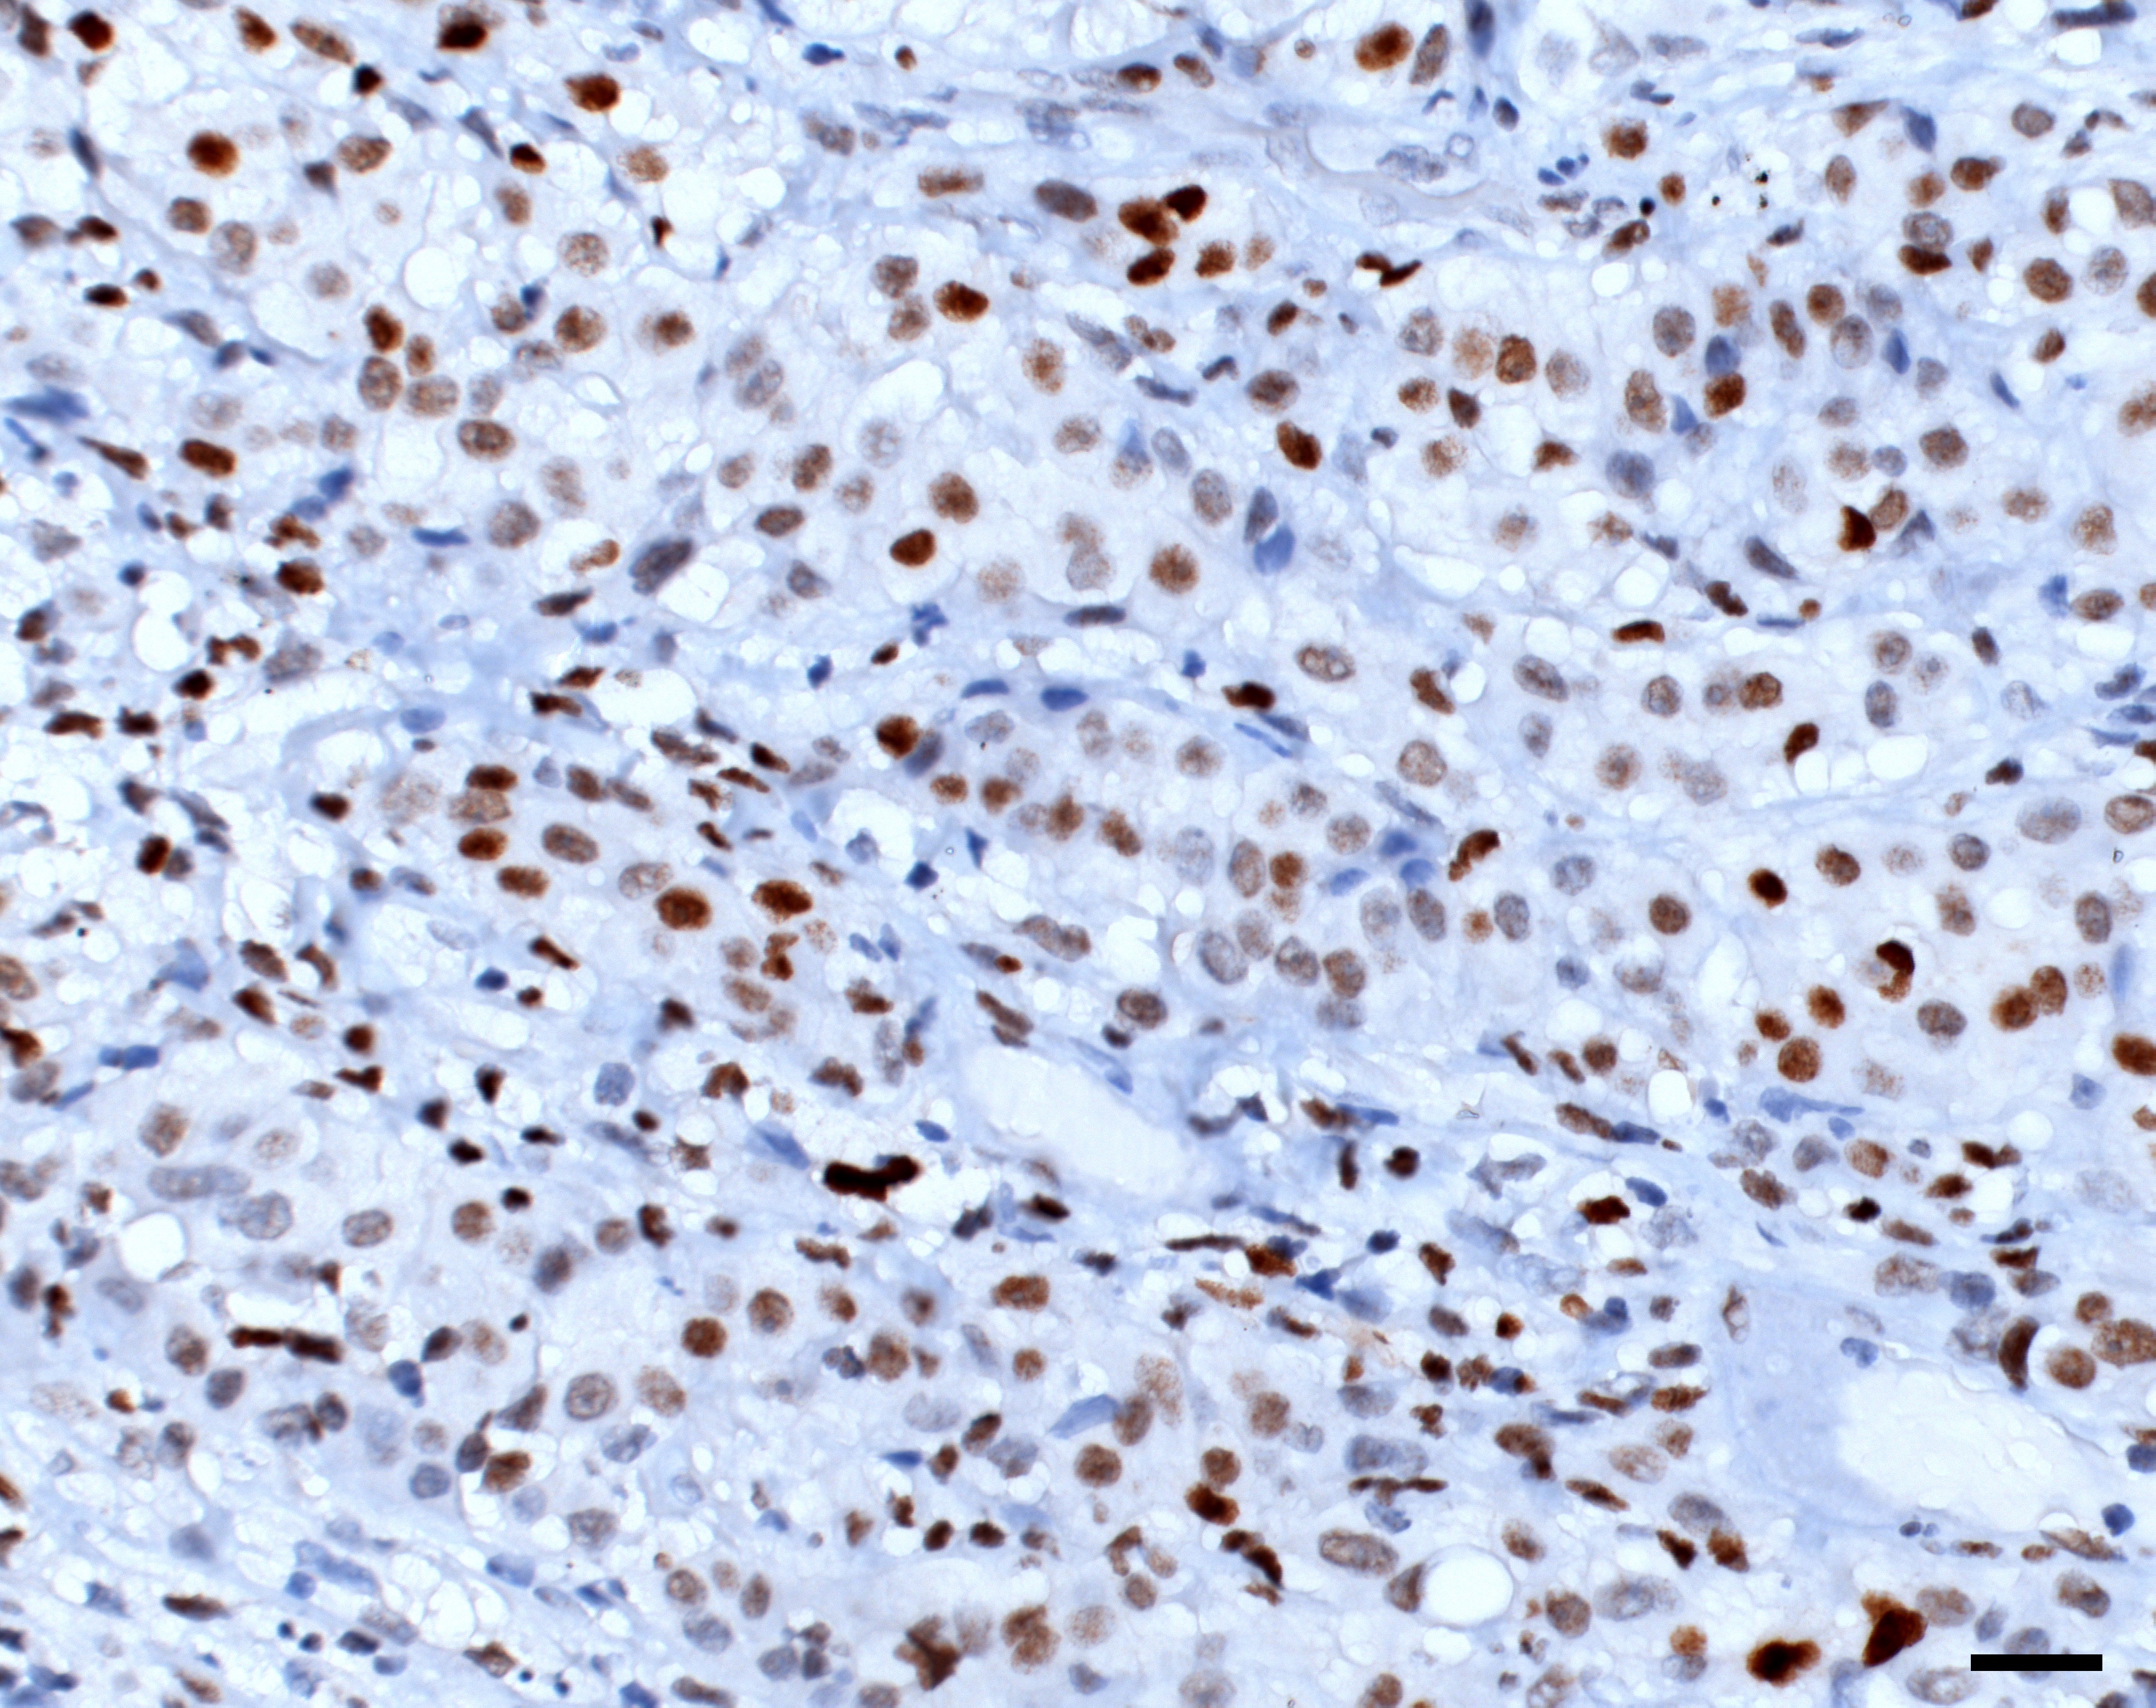

In order to find the vulnerabilities of cancer cells and treat cancer, we need to understand the biology of cancer. How do cancer cells differ from healthy cells, and how do they interact with their environment, or with therapies?

How do cancer cells differ from normal cells?

How do various cell types in the body affect the development of cancer and its response to treatment?